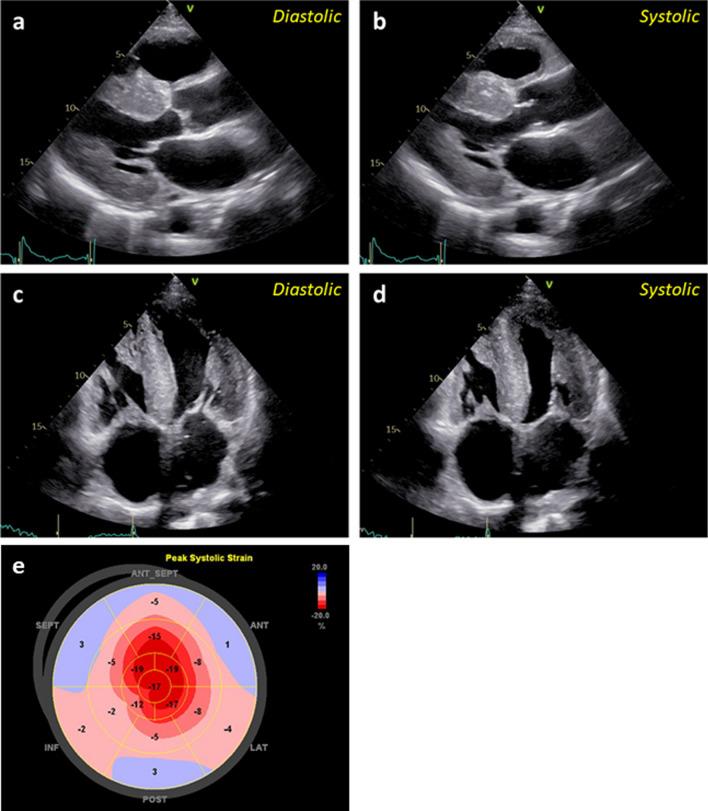

A 72-year-old man with cardiac hypertrophy presented with New York Heart Association functional class III dyspnea and leg edema. He had no history of carpal tunnel syndrome. An electrocardiogram showed atrial fibrillation and low voltage. The N-terminal pro-B-type natriuretic peptide level was 3310 pg/mL, and troponin T was elevated to 0.073 ng/mL. However, the glomerular filtration rate was only slightly decreased at 69.0 mL/min/1.73 m. The serum free light-chain assay revealed a significant increase in the kappa chain, with positive results in Bence Jones proteins and serum immunoelectrophoresis. Bone marrow examination confirmed the diagnosis of monoclonal gammopathy of undetermined significance (MGUS). AL-type amyloidosis associated with a myeloproliferative disorder was suspected, and the prognosis was initially predicted to be poor, classified as Mayo stage IV. Contrary to this prognosis, the patient showed a slow progression of heart failure. Further imaging modalities and cardiac tissue findings confirmed the diagnosis as transthyretin type amyloidosis, and a favorable prognosis was established with the use of tafamidis.